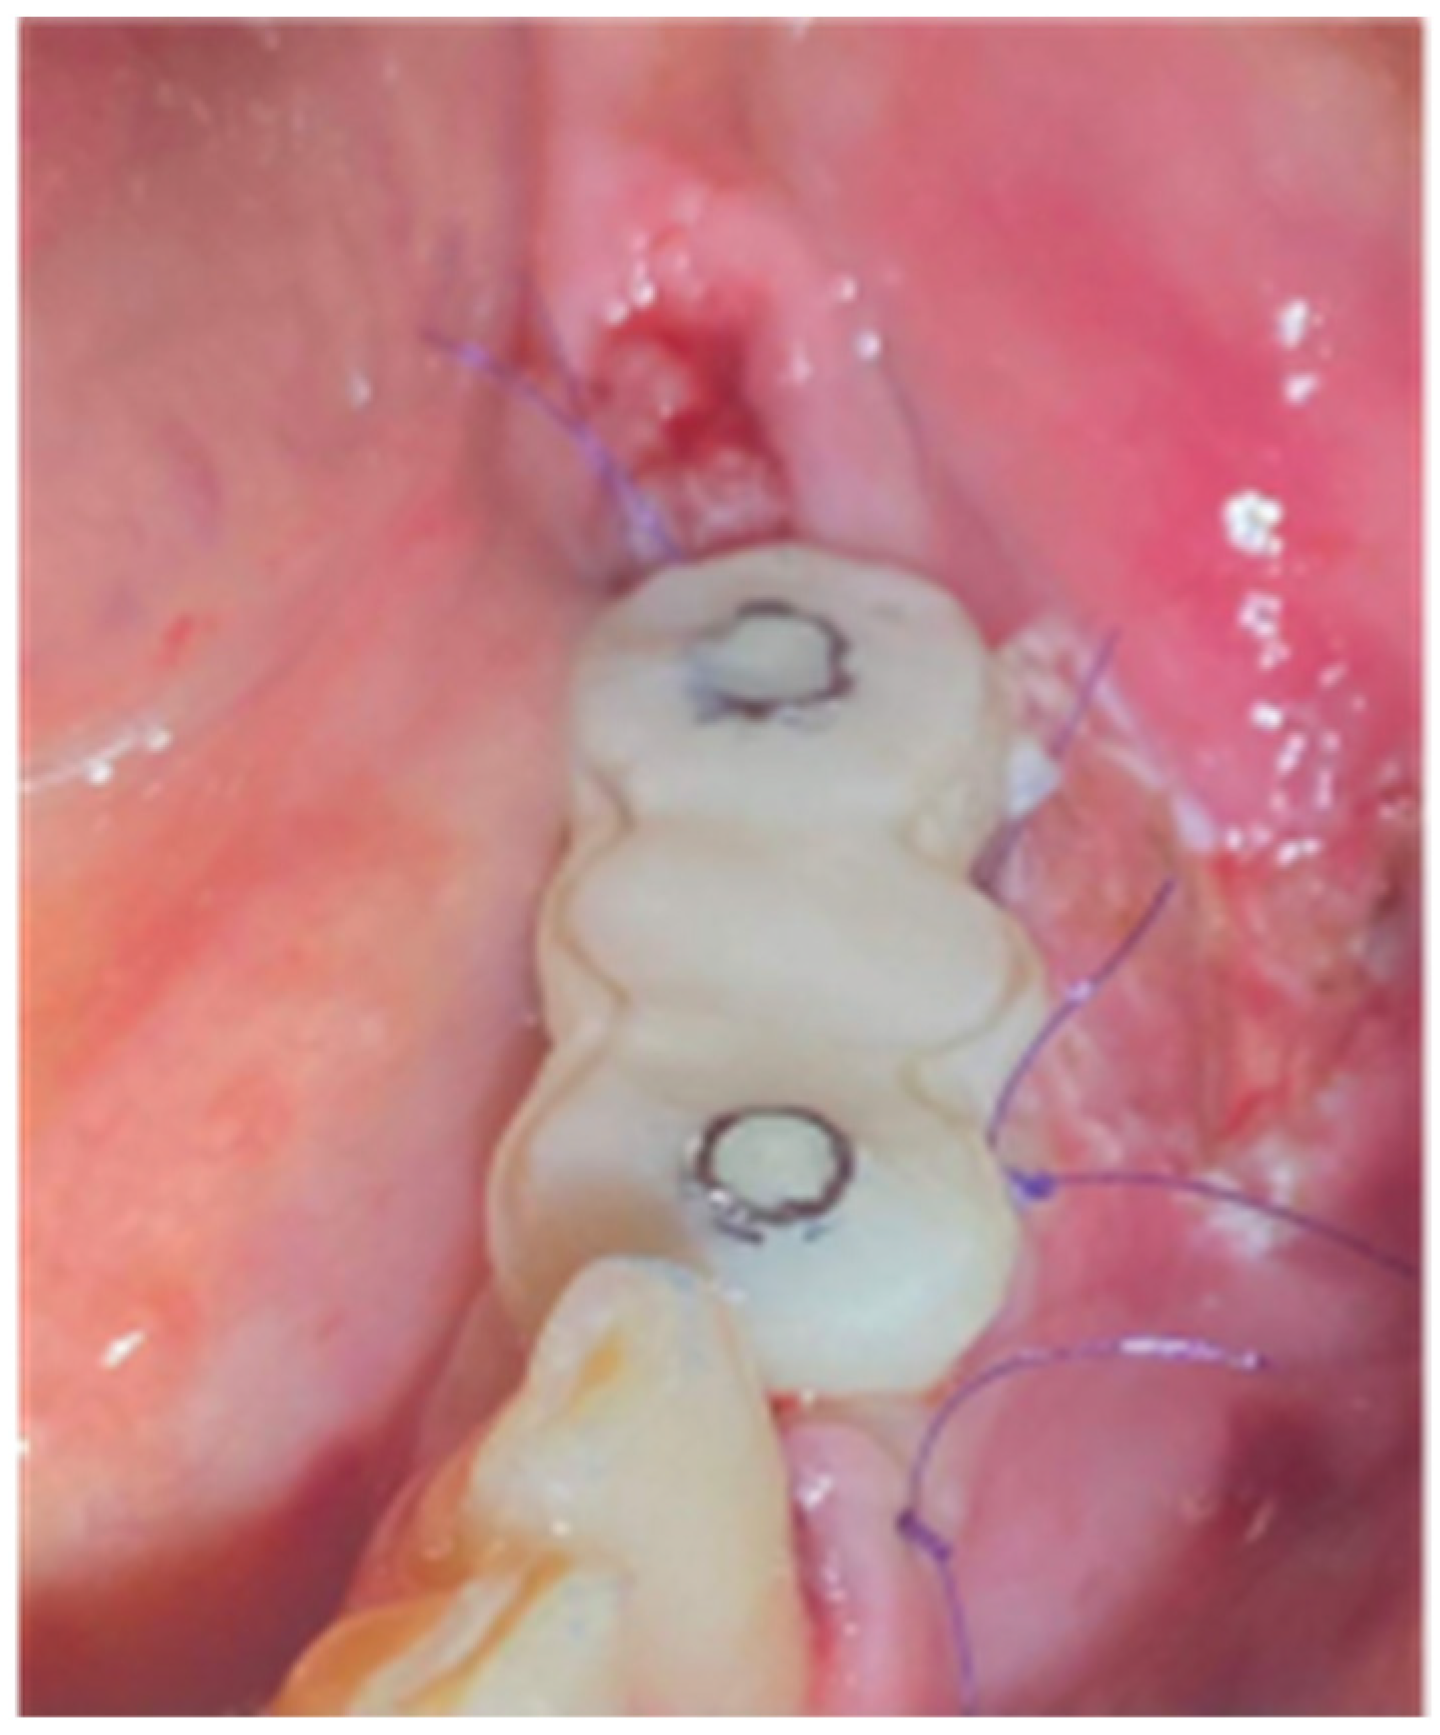

The 2 anatomical VPI Cervico abutments were placed and secured over the implants after their surface was disinfected with alcohol and cleaned with a steamer. The 2 flaps were then secured around the abutments with 5.0 silk interrupted sutures and compressed trimmed pure collagen (Spongostan - Ethicon Inc, Somerville, USA) was used in the interproximal areas to fill the spaces between the flaps’ marginal edges (Figure 15). The same post surgical instructions, as in Stage 1 procedure, were given to the patient and Azithromycin 500 mgr was prescribed (1g single same day dose) to enhance the soft tissue healing.

Figure 15. Replacement of the stock abutments by VPI Crevice abutments and flap closure by adding collagen sponges within inter proximal areas.